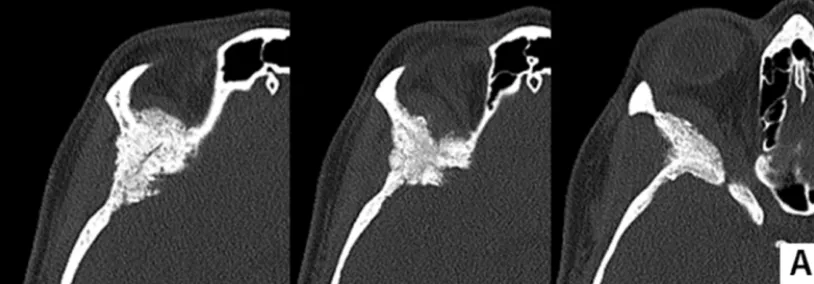

术前计算机断层扫描图像(骨窗)显示由蝶眶脑膜瘤引起的增生,涉及蝶骨大翼、蝶骨小翼、前床突以及眼眶上壁以及颞骨鳞部。